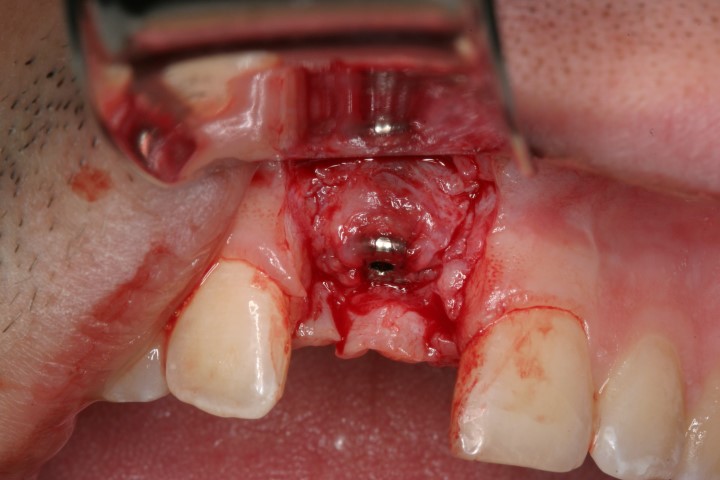

ביצוע ההשתלה עם עיבוי העצם (אוגמנטציה)